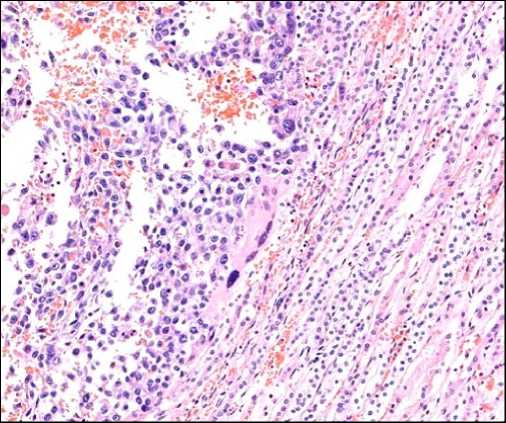

Результаты прижизненного гистологического исследования операционного материала легкого показали инфильтративный рост солидной злокачественной опухоли с высокой клеточной атипией, митозами и очаговыми кровоизлияниями. Опухолевые клетки экспрессировали PanCK (большая часть клеток), Glypican3 (единичные клетки), не окрашивались с CD117, TTF1, CD30, p63, OCT4, CD34, CD31, D240, AFP (рис. 1).

Рис. 1. Злокачественная опухоль в операционном материале легкого: a – атипичные клетки среди масс крови (окраска гематоксилином и эозином, ×40); b – негативная реакция с AFP (×20); с – экспрессия единичными клетками Glypican3 (×40)